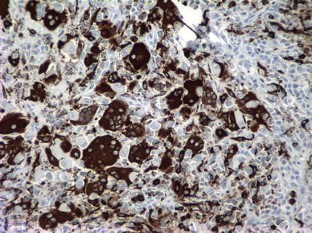

Soft tissue giant cell tumor of low malignant potential is a rare tumor located in superficial and deep soft tissue. Tumors with osteoclast-like giant cells have been reported in various sites as breast, salivary glands, lung, kidney and pancreas. These tumors are composed of evenly spaced multinucleated giant cells in a background of mononuclear component composed of round, oval or spindled cells. No atypia or significant mitotic activity is encountered. Immunohistochemical stains for TRAP, smooth muscle actin, desmin and cytokeratins are of great value for diagnosis. Nasal cavity represents a very unusual location for this type of tumors; soft tissue tumors must be included in the differential diagnosis of nasal obstruction. Due to the possibility of local recurrence, clinical follow-up is recommended.

Fig. 2